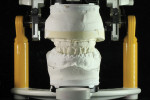

As in all prosthodontic procedures the case begins with the patient, and understanding their esthetic needs and expectations through visual observation and digital photography. After the master casts have been created and mounted according to clinical relationship records the restorative space needed is evaluated.

Measurements and calculations are made to determine proper bone reduction after extraction of remaining dentition. The space calculation is determined from the 10-mm tooth, the 4-mm bar, and 4-mm wrap around acrylic. It is determined that 15 mm on the anterior and 13 mm on the posterior sector are needed or the final restoration (Figure 2 through Figure 5). This bone reduction measurement will guide the clinical and technical restorative team in the design and fabrication for this immediate-loaded implant prosthesis. A silicone putty occlusal registration should always be created before master cast surgery to remove teeth, tissue, and bone (Figure 6). This will provide a reference point in case one needs to verify the starting point at anytime. The master cast is then sectioned and removed (Figure 7 and Figure 8).